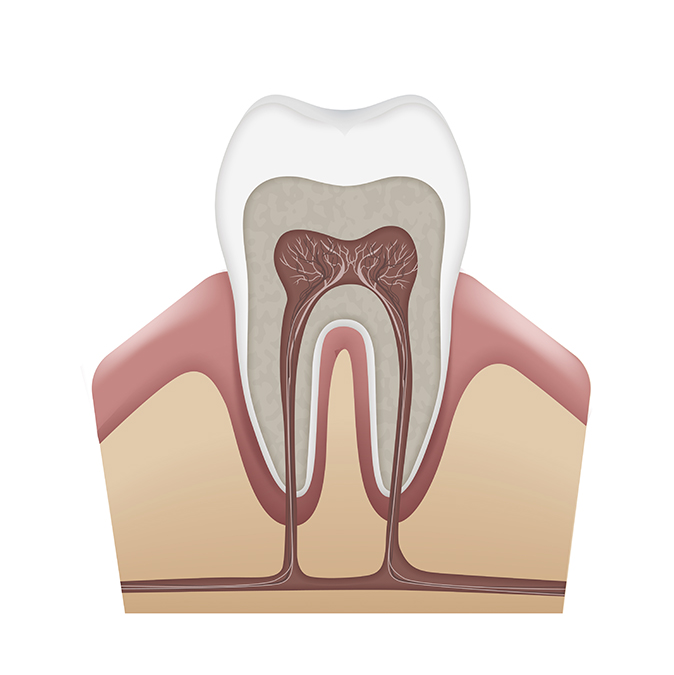

Es una especialidad dentro de la Odontología que se preocupa de la salud de los tejidos que le dan soporte y protección a los dientes e implantes, es decir, los tejidos en contacto con la raíz del diente: hueso del maxilar (cemento que cubre la raíz del diente) y un...